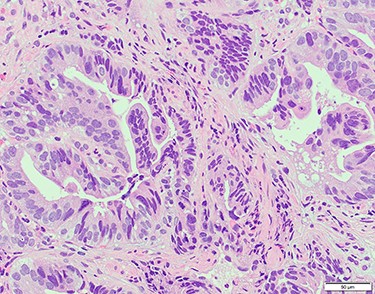

Chest and abdominal computed tomography (CT) showed no distant metastasis, but the tumor of the antrum was clearly visualized and was located close to the pancreatic head (Fig. 1). EGD revealed a large ulcerated lesion at the greater curvature of the antrum (Fig. 2). Hematoxylin and eosin staining of the biopsy specimen of the tumor confirmed a well-differentiated adenocarcinoma (tub1, tub2) (Fig. 3). The assessment of the HER2 expression by immunohistochemistry revealed the overexpression of HER2 (3+) in the biopsy tissue of the gastric tumor (Fig. 4).

Hematoxylin and eosin staining of the biopsy specimen of the tumor confirmed a well-differentiated adenocarcinoma (tub1, tub2).